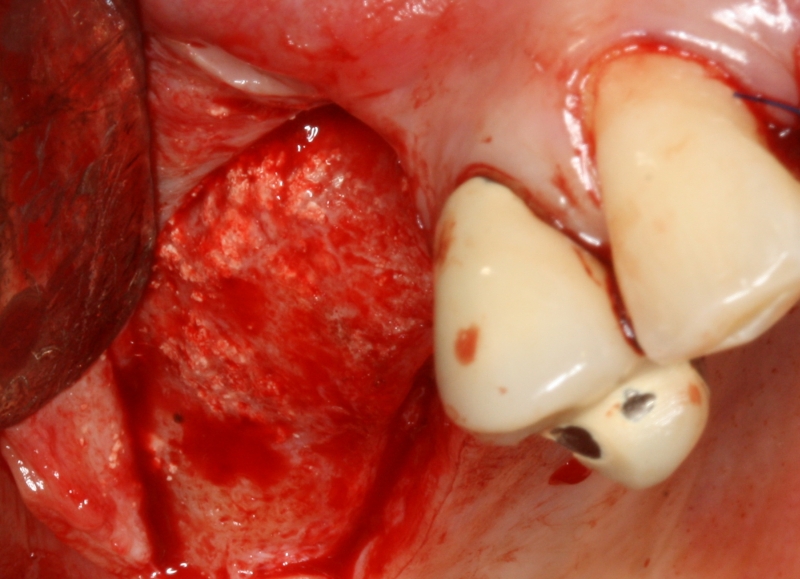

08/20 - Surgical presentation of the alveolar ridgeGBR with maxresorb® & Jason® membrane - Prof. Dr. Dr. D. Rothamel

-